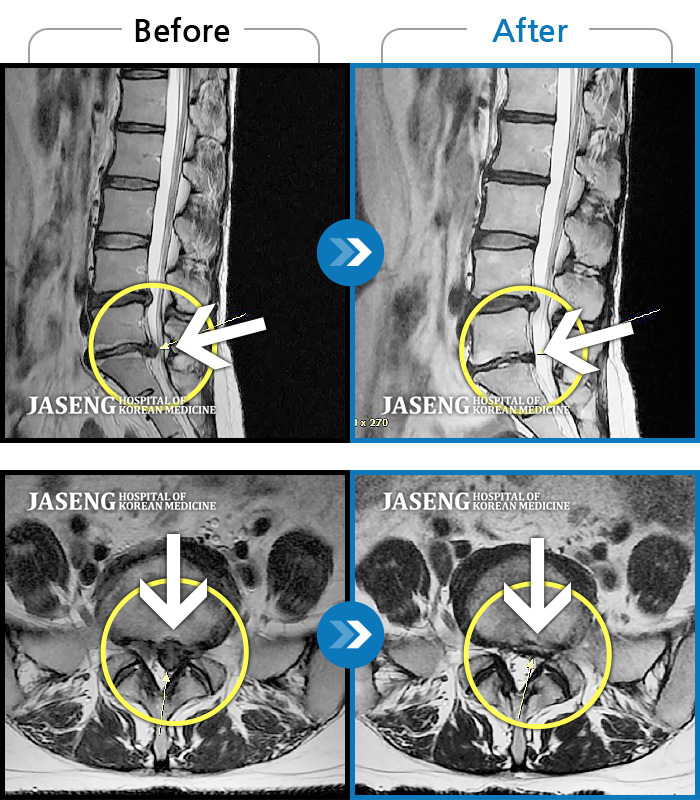

허리디스크

울산 · 정운석 원장

우측 하요추부 통증-우측 둔부-소퇴 후면 통증/비증

촬영시기

2021.08.08 ~ 2021.08.13

2021.08.20